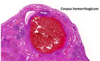

corpus hemorrhagicum

מה בסלייד?

- corpus hemorrhagicum (גוף מדמם באופן טבעי עקב קריעה של קפילרות)